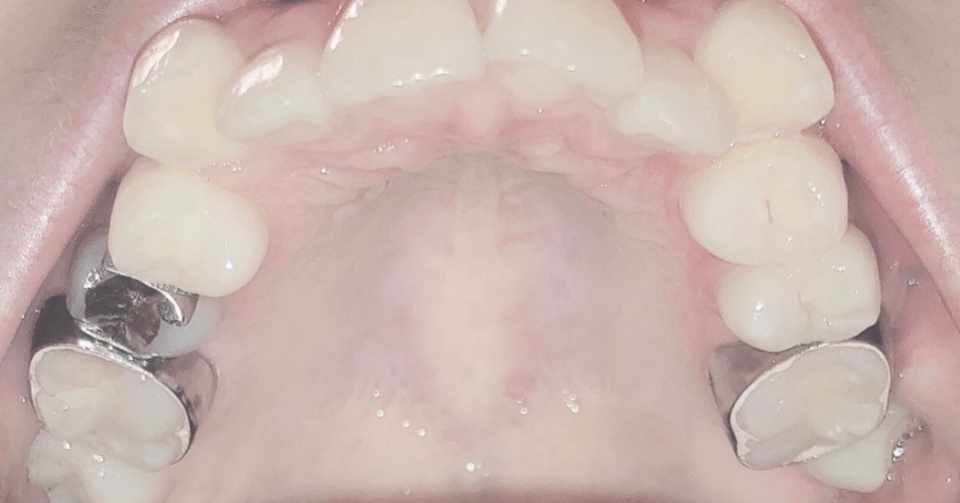

歯列矯正を始めます まだ青ゴムの段階ですが画像のように装置一 Yahoo 知恵袋